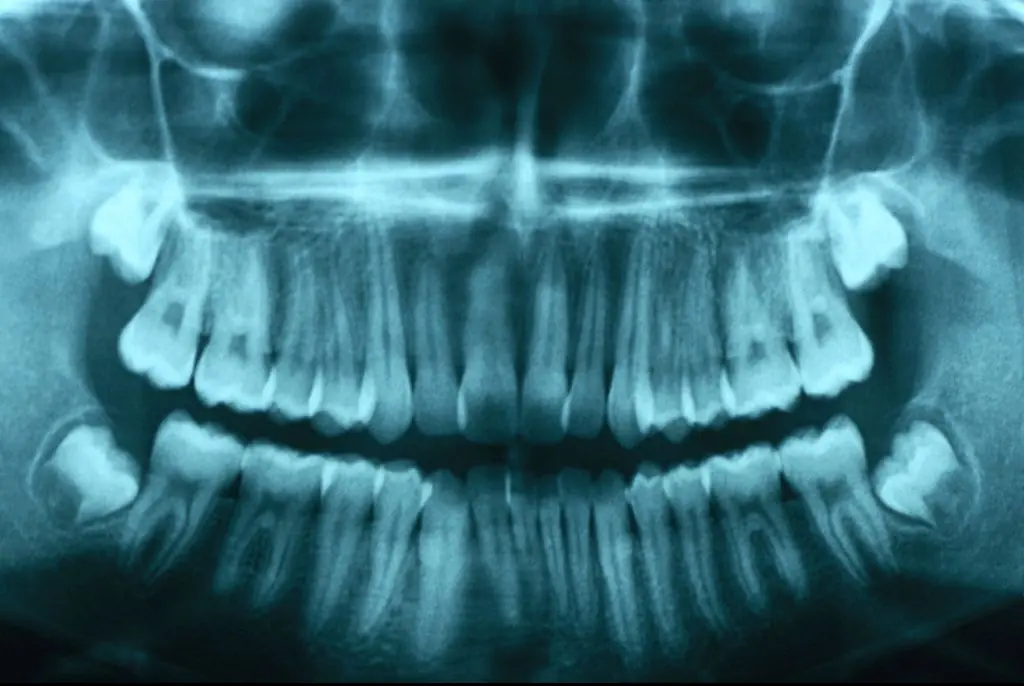

A CT scan eventually revealed the source of Alsop's life-threatening condition was an impacted and infected wisdom tooth.

Emergency surgery was performed to remove the tooth, and additional procedures were required to relieve pressure on her jugular vein.